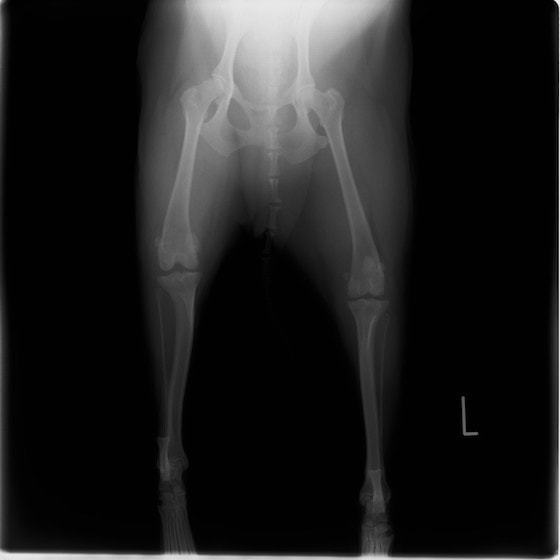

左後肢の挙上を主訴に来院されました。触診にて両関節の前方引き出し兆候、両膝蓋骨の内方脱臼を認めました。関節液検査より免疫介在性多発性関節炎は否定的でした。レントゲン検査にてfat pad signを伴う関節炎が認められたことから、前十字靭帯断裂と膝蓋骨内方脱臼(左GradeⅢ 右GradeⅢ〜IV)併発と診断し、手術を行いました。

手術は片足ずつ行い、両膝とも術中の関節鏡検査にて前十字靭帯の完全断裂と半月板損傷を確認しました。TPLO、半月板切除と滑車溝形成を始めとした膝蓋骨脱臼整復術を実施いたしました。膝蓋骨の安定化を測るために外側支帯を強固に縫合し、内側支帯は切除し縫合せずに開放状態にしています。

術後の歩行状態は良好です。

術前正面像

術前のTPAは左後肢33.1°右後肢26.8°でしたがTPLO実施により左後肢5.5°右後肢12°に矯正されました。